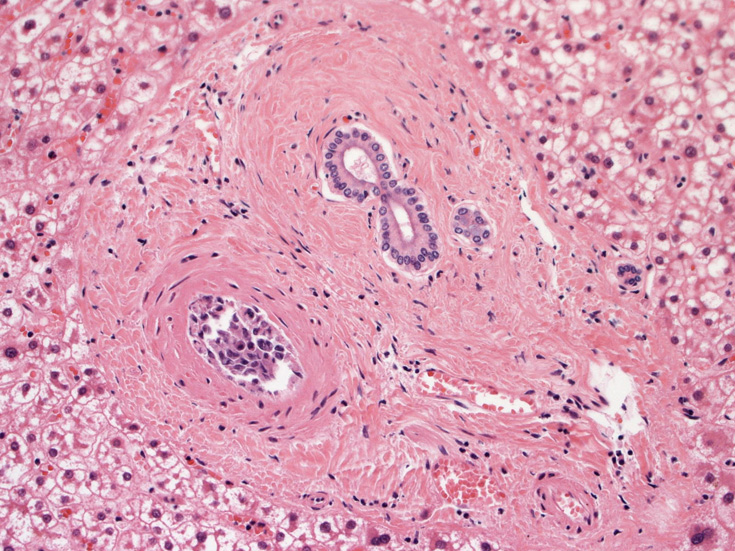

心臓;比較的大きな冠動脈内で増殖。作成した標本では心筋内細血管内には認めなかった。

肝臓;グリソン鞘内、細肝動脈に腫瘍細胞あり。肝細胞は虚血のため変性しているようです。